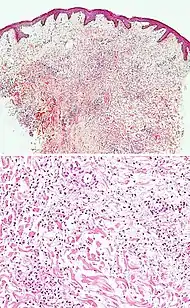

| Pigmented purpuric dermatosis |

|

![]() |